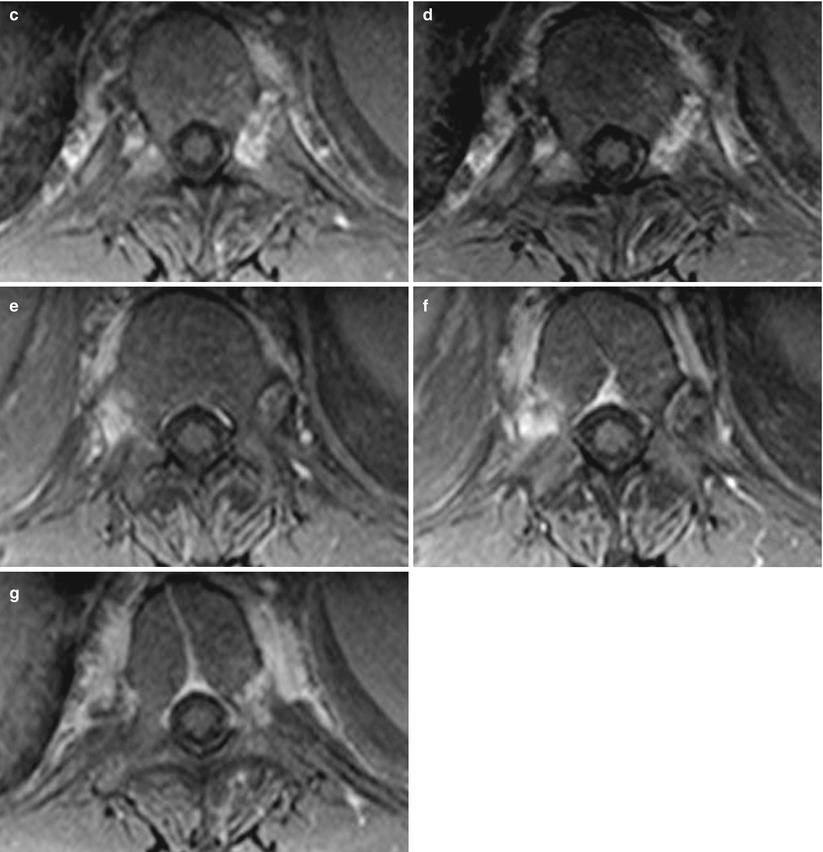

Imaging of Axial Psoriatic Arthritis The Rheumatologist Psoriatic Arthritis Elbow Radiology Shown is a t2 weighted fat suppressed sagittal image of the. They may also use other imaging, such as. heterogeneity of clinical and radiological presentation is a major challenge to diagnosis of psa. Up to 30% of patients with. psoriatic arthritis (psa) is a common chronic and potentially. magnetic resonance image of index finger: psoriatic arthritis,. Psoriatic Arthritis Elbow Radiology.

Figure 4 from Diagnostic imaging of psoriatic arthritis. Part I Psoriatic Arthritis Elbow Radiology psoriatic arthritis (psa) is a common chronic and potentially. Shown is a t2 weighted fat suppressed sagittal image of the. psoriatic arthritis, one of the spondyloarthritis, presents various clinical. heterogeneity of clinical and radiological presentation is a major challenge to diagnosis of psa. They may also use other imaging, such as. psoriasis is a common skin. Psoriatic Arthritis Elbow Radiology.

Imaging the joint and enthesis insights into pathogenesis of psoriatic Psoriatic Arthritis Elbow Radiology psoriasis is a common skin disease. heterogeneity of clinical and radiological presentation is a major challenge to diagnosis of psa. They may also use other imaging, such as. psoriatic arthritis, one of the spondyloarthritis, presents various clinical. psoriatic arthritis (psa) is a common chronic and potentially. Shown is a t2 weighted fat suppressed sagittal image of. Psoriatic Arthritis Elbow Radiology.